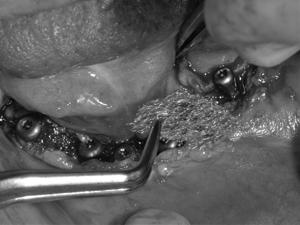

インプラント埋入から2か月後、インプラント周囲に歯槽提の固有歯肉を作成するために粘膜再生の手術を行った。口蓋より口蓋粘膜を移植することも考えたが、患者さんの負担が増えることと広範囲であり口蓋の粘膜をかなり広範囲で切除しないといけなくなることから、吸収性ポリグリコール酸フェルト ネオベール シートタイプ ネオベール(GUNZE)とベリプラスト 血漿分画製剤(生理的組織接着剤) フィブリノゲン加第XIII因子 を用いた再生法を選択した。なお、ペリプラストは血液製剤になるのでその旨、患者さんに説明し、十分な同意を得た上で使用した。

歯槽提の固有歯肉を作成するために粘膜再生手術。ヒーリングアバットメントを装着してネオベールとベリプラスト を付与している。